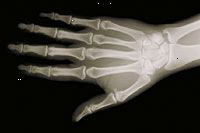

Οι ακτίνες Χ γίνονται με τη χρήση εξωτερικών ακτινοβολία για να παράγει εικόνες του σώματος, τα όργανά του, και άλλες εσωτερικές δομές για διαγνωστικούς σκοπούς. Ακτίνες Χ διέρχεται μέσα από τις δομές του σώματος πάνω σε πλάκες, ειδικά επεξεργασμένο (παρόμοια με τα φωτογραφικά φιλμ) ή ψηφιακών μέσων και μια «αρνητική» εικόνα τύπου γίνεται (η πιο σταθερή είναι μια δομή, τα λευκά εμφανίζεται στην ταινία).

Όταν το σώμα υποβάλλεται σε ακτίνες Χ, διαφορετικά μέρη του σώματος επιτρέπουν ποικίλες ποσότητες των δοκών ακτίνων Χ για να περάσει μέσα. Οι μαλακοί ιστοί του σώματος (όπως αίμα, το δέρμα, το λίπος, και των μυών) επιτρέπουν το μεγαλύτερο μέρος της Χ-Χ για να περάσει μέσα και εμφανίζονται σκούρα γκρι στο φιλμ ή ψηφιακά μέσα. Ένα οστών ή ένας όγκος, που είναι πιο πυκνό από μαλακούς ιστούς, επιτρέπει μερικές από τις ακτίνες Χ για να περάσει μέσα και εμφανίζεται λευκό για την ακτινογραφία. Σε ένα διάλειμμα σε ένα οστό, η δέσμη ακτίνων Χ περνά μέσα από το σπασμένο περιοχή και εμφανίζεται ως μια σκοτεινή γραμμή στο λευκό οστό.